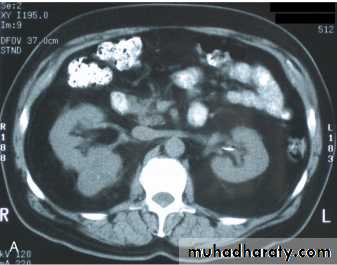

Ct enhanced

Big simple renal cyst(non enhancing mass homogenous) treatment is conservative or drainge if symptomaticWhat's the Diagnosis?